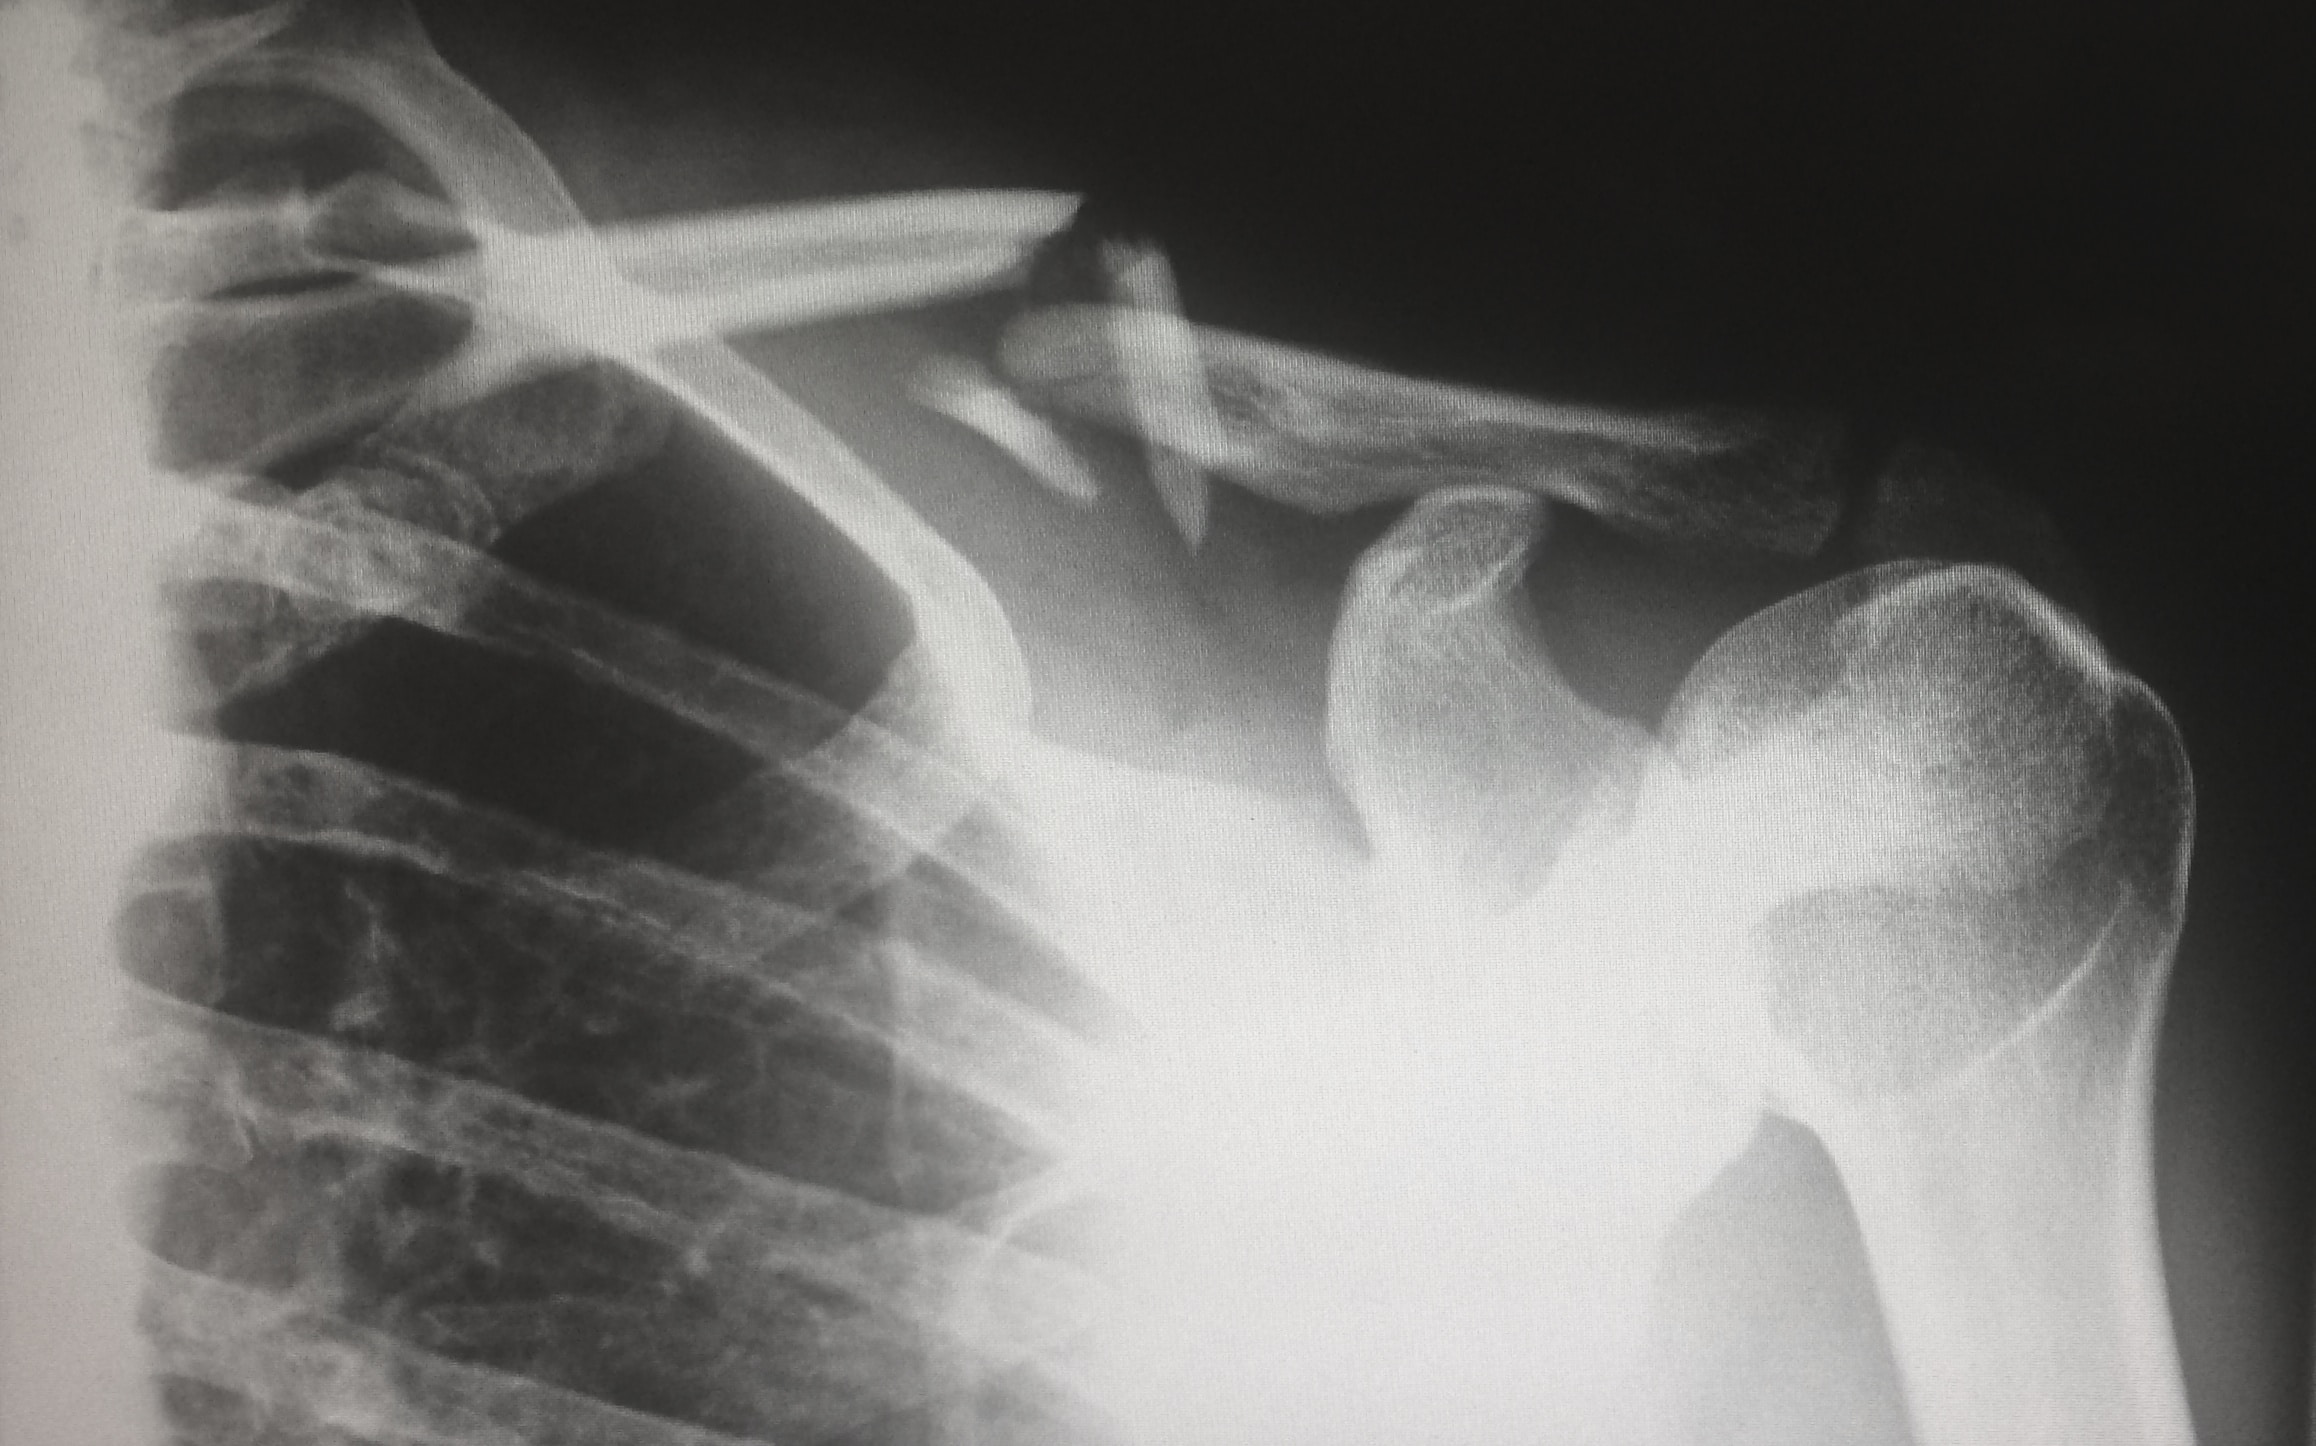

오십견은 주로 어깨와 상완골 사이의 관절인 견관절에서 발생하는 질병이나 장애를 가리키는 용어입니다. 주로 오십견 증후군(SIS, Shoulder Impingement Syndrome)이라고도 알려져 있습니다.

오십견은 견관절 주변의 구조에 염증이나 손상이 발생하여 발생할 수 있습니다. 이러한 구조에는 견봉의 힘줄, 힘줄의 건, 견봉의 힘줄과 견봉 사이의 점막, 견봉 아래의 점막 등이 포함됩니다. 견관절에서 발생한 염증 또는 손상은 통증, 불편함, 움직임 제한 및 기능 장애를 유발할 수 있습니다.